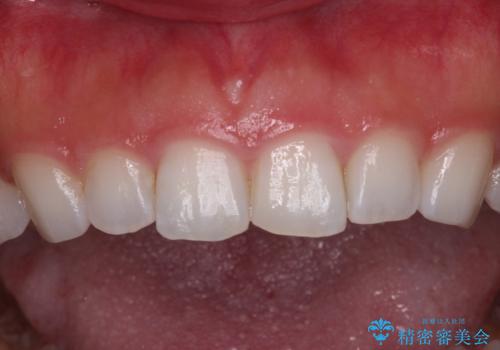

- 矯正治療で歯列を整えた後、前歯の形が気になった患者様です。

矯正前の歯列の影響で、前歯の先端が非対称にすり減ってしまったため、矯正治療後の形が非対称になっていました。

むし歯はなく、矯正治療で咬み合わせが改善していたので、侵襲量の少ないラミネートベニアにて治療することとしました。